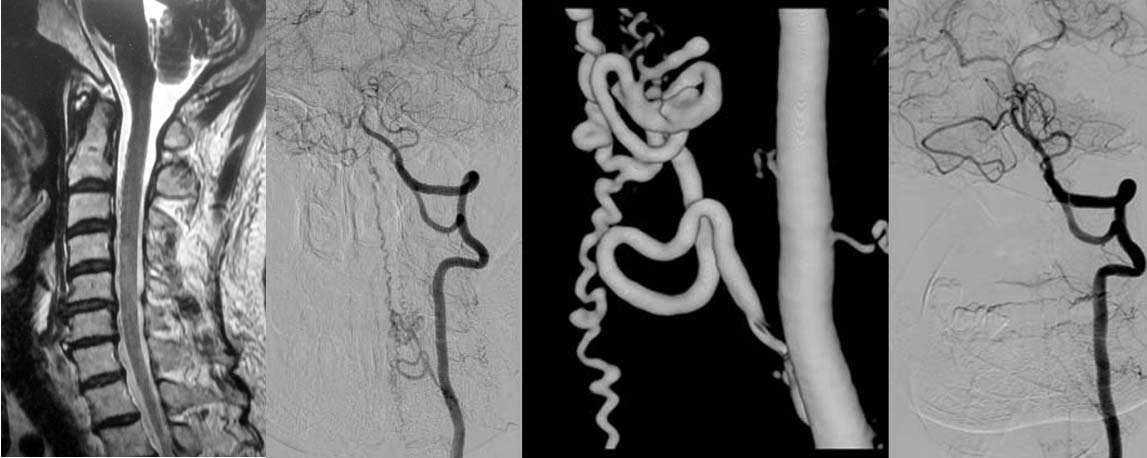

図1.頚椎MRIでは脊髄の周辺にプツプツとした小さな陰影がみられますが、詳細はわかりません。造影剤を用いたカテーテル検査(左椎骨動脈撮影)では異常血管が描出され、脊髄硬膜動静脈瘻であると診断出来ます。下記手術を行い、異常血管は消失しました。

神経所見を診察し、MRI等を施行し脊髄梗塞や出血の診断をします。しかし、脊髄の血管は細かいためMRIだけでは診断は難しく、造影剤を用いたカテーテル検査が必要です。